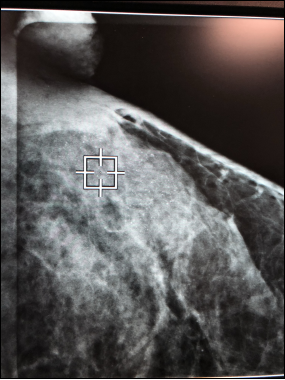

5月11日,乳腺外一科在乳腺钼靶下成功定位1例病。

图片1.png

图表1:乳腺X线下病灶定位操作中